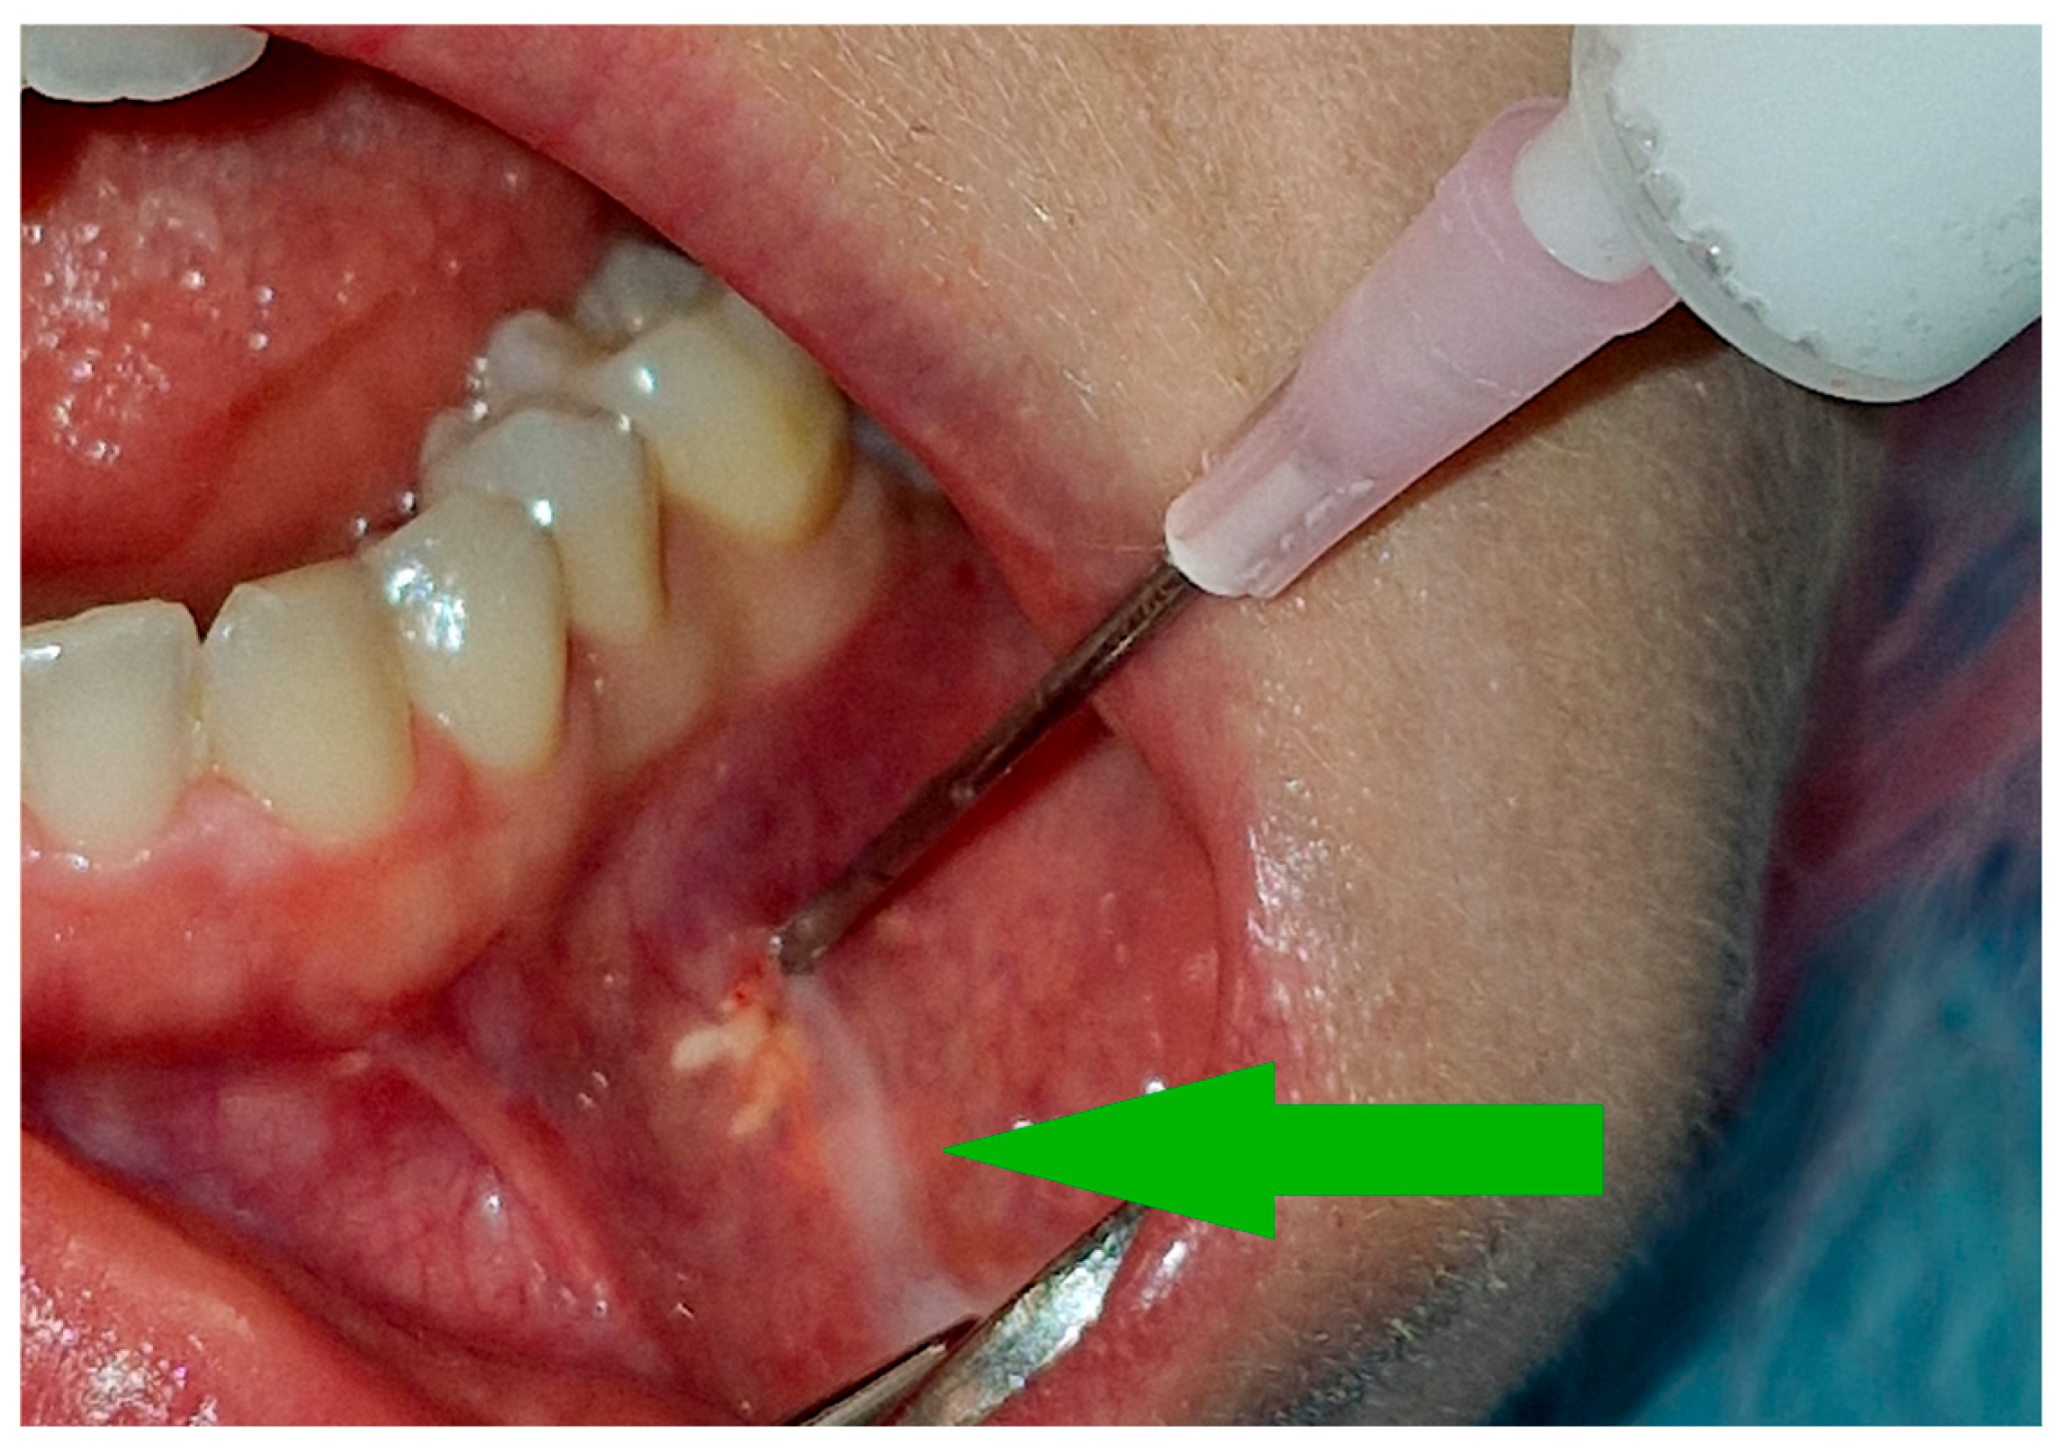

3.2. Injections